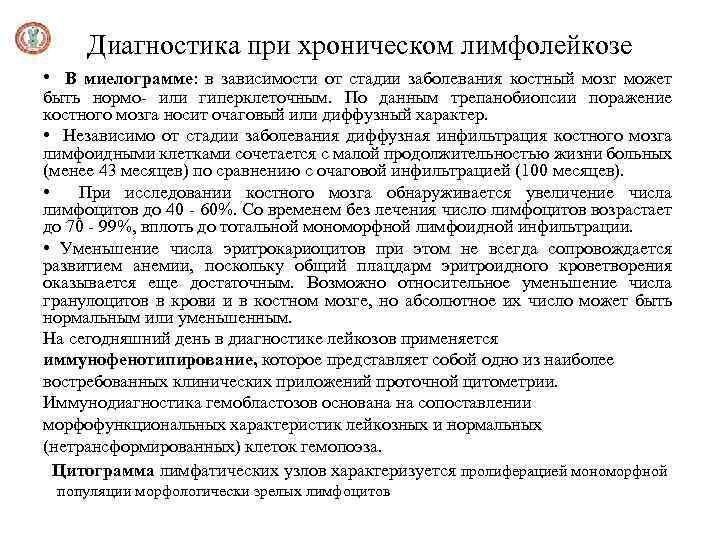

Диагностика при хроническом лимфолейкозе • В миелограмме: в зависимости от стадии заболевания костный мозг может быть нормо- или гиперклеточным. По данным трепанобиопсии поражение костного мозга носит очаговый или диффузный характер. • Независимо от стадии заболевания диффузная инфильтрация костного мозга лимфоидными клетками сочетается с малой продолжительностью жизни больных (менее 43 месяцев) по сравнению с очаговой инфильтрацией (100 месяцев). • При исследовании костного мозга обнаруживается увеличение числа лимфоцитов до 40 - 60%. Со временем без лечения число лимфоцитов возрастает до 70 - 99%, вплоть до тотальной мономорфной лимфоидной инфильтрации. • Уменьшение числа эритрокариоцитов при этом не всегда сопровождается развитием анемии, поскольку общий плацдарм эритроидного кроветворения оказывается еще достаточным. Возможно относительное уменьшение числа гранулоцитов в крови и в костном мозге, но абсолютное их число может быть нормальным или уменьшенным. На сегодняшний день в диагностике лейкозов применяется иммунофенотипирование, которое представляет собой одно из наиболее востребованных клинических приложений проточной цитометрии. Иммунодиагностика гемобластозов основана на сопоставлении морфофункциональных характеристик лейкозных и нормальных (нетрансформированных) клеток гемопоэза. Цитограмма лимфатических узлов характеризуется пролиферацией мономорфной популяции морфологически зрелых лимфоцитов